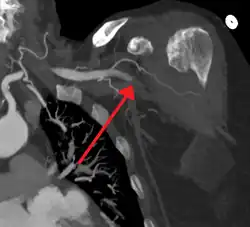

Acute embolism to the right femoral artery resulting in ischemia | |